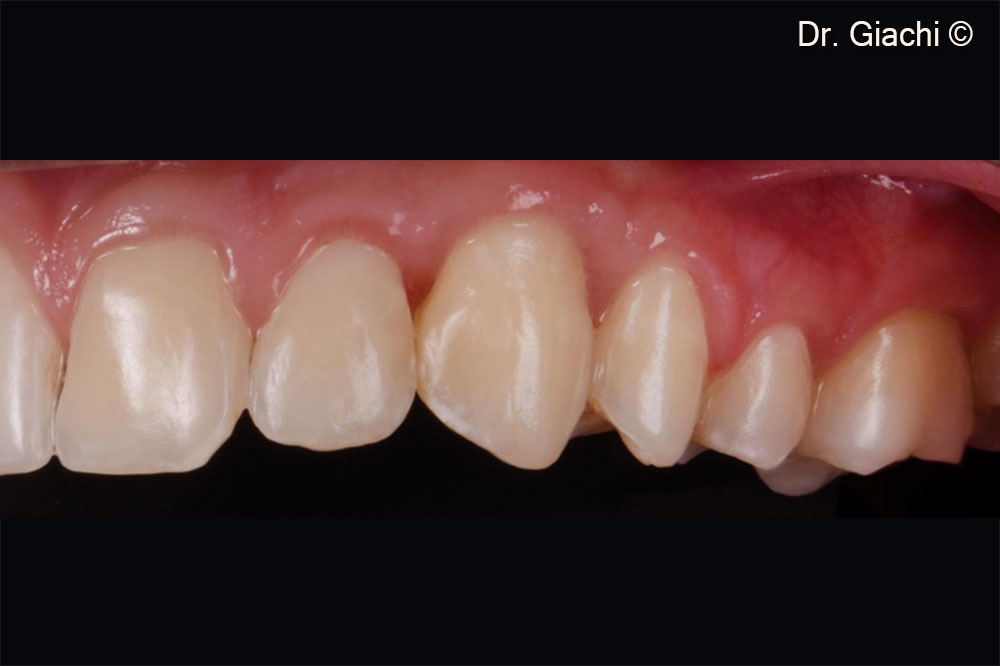

Một bệnh nhân nam (16 tuổi) có răng nanh trên không thể phục hồi bằng phương pháp chỉnh nha truyền thống.